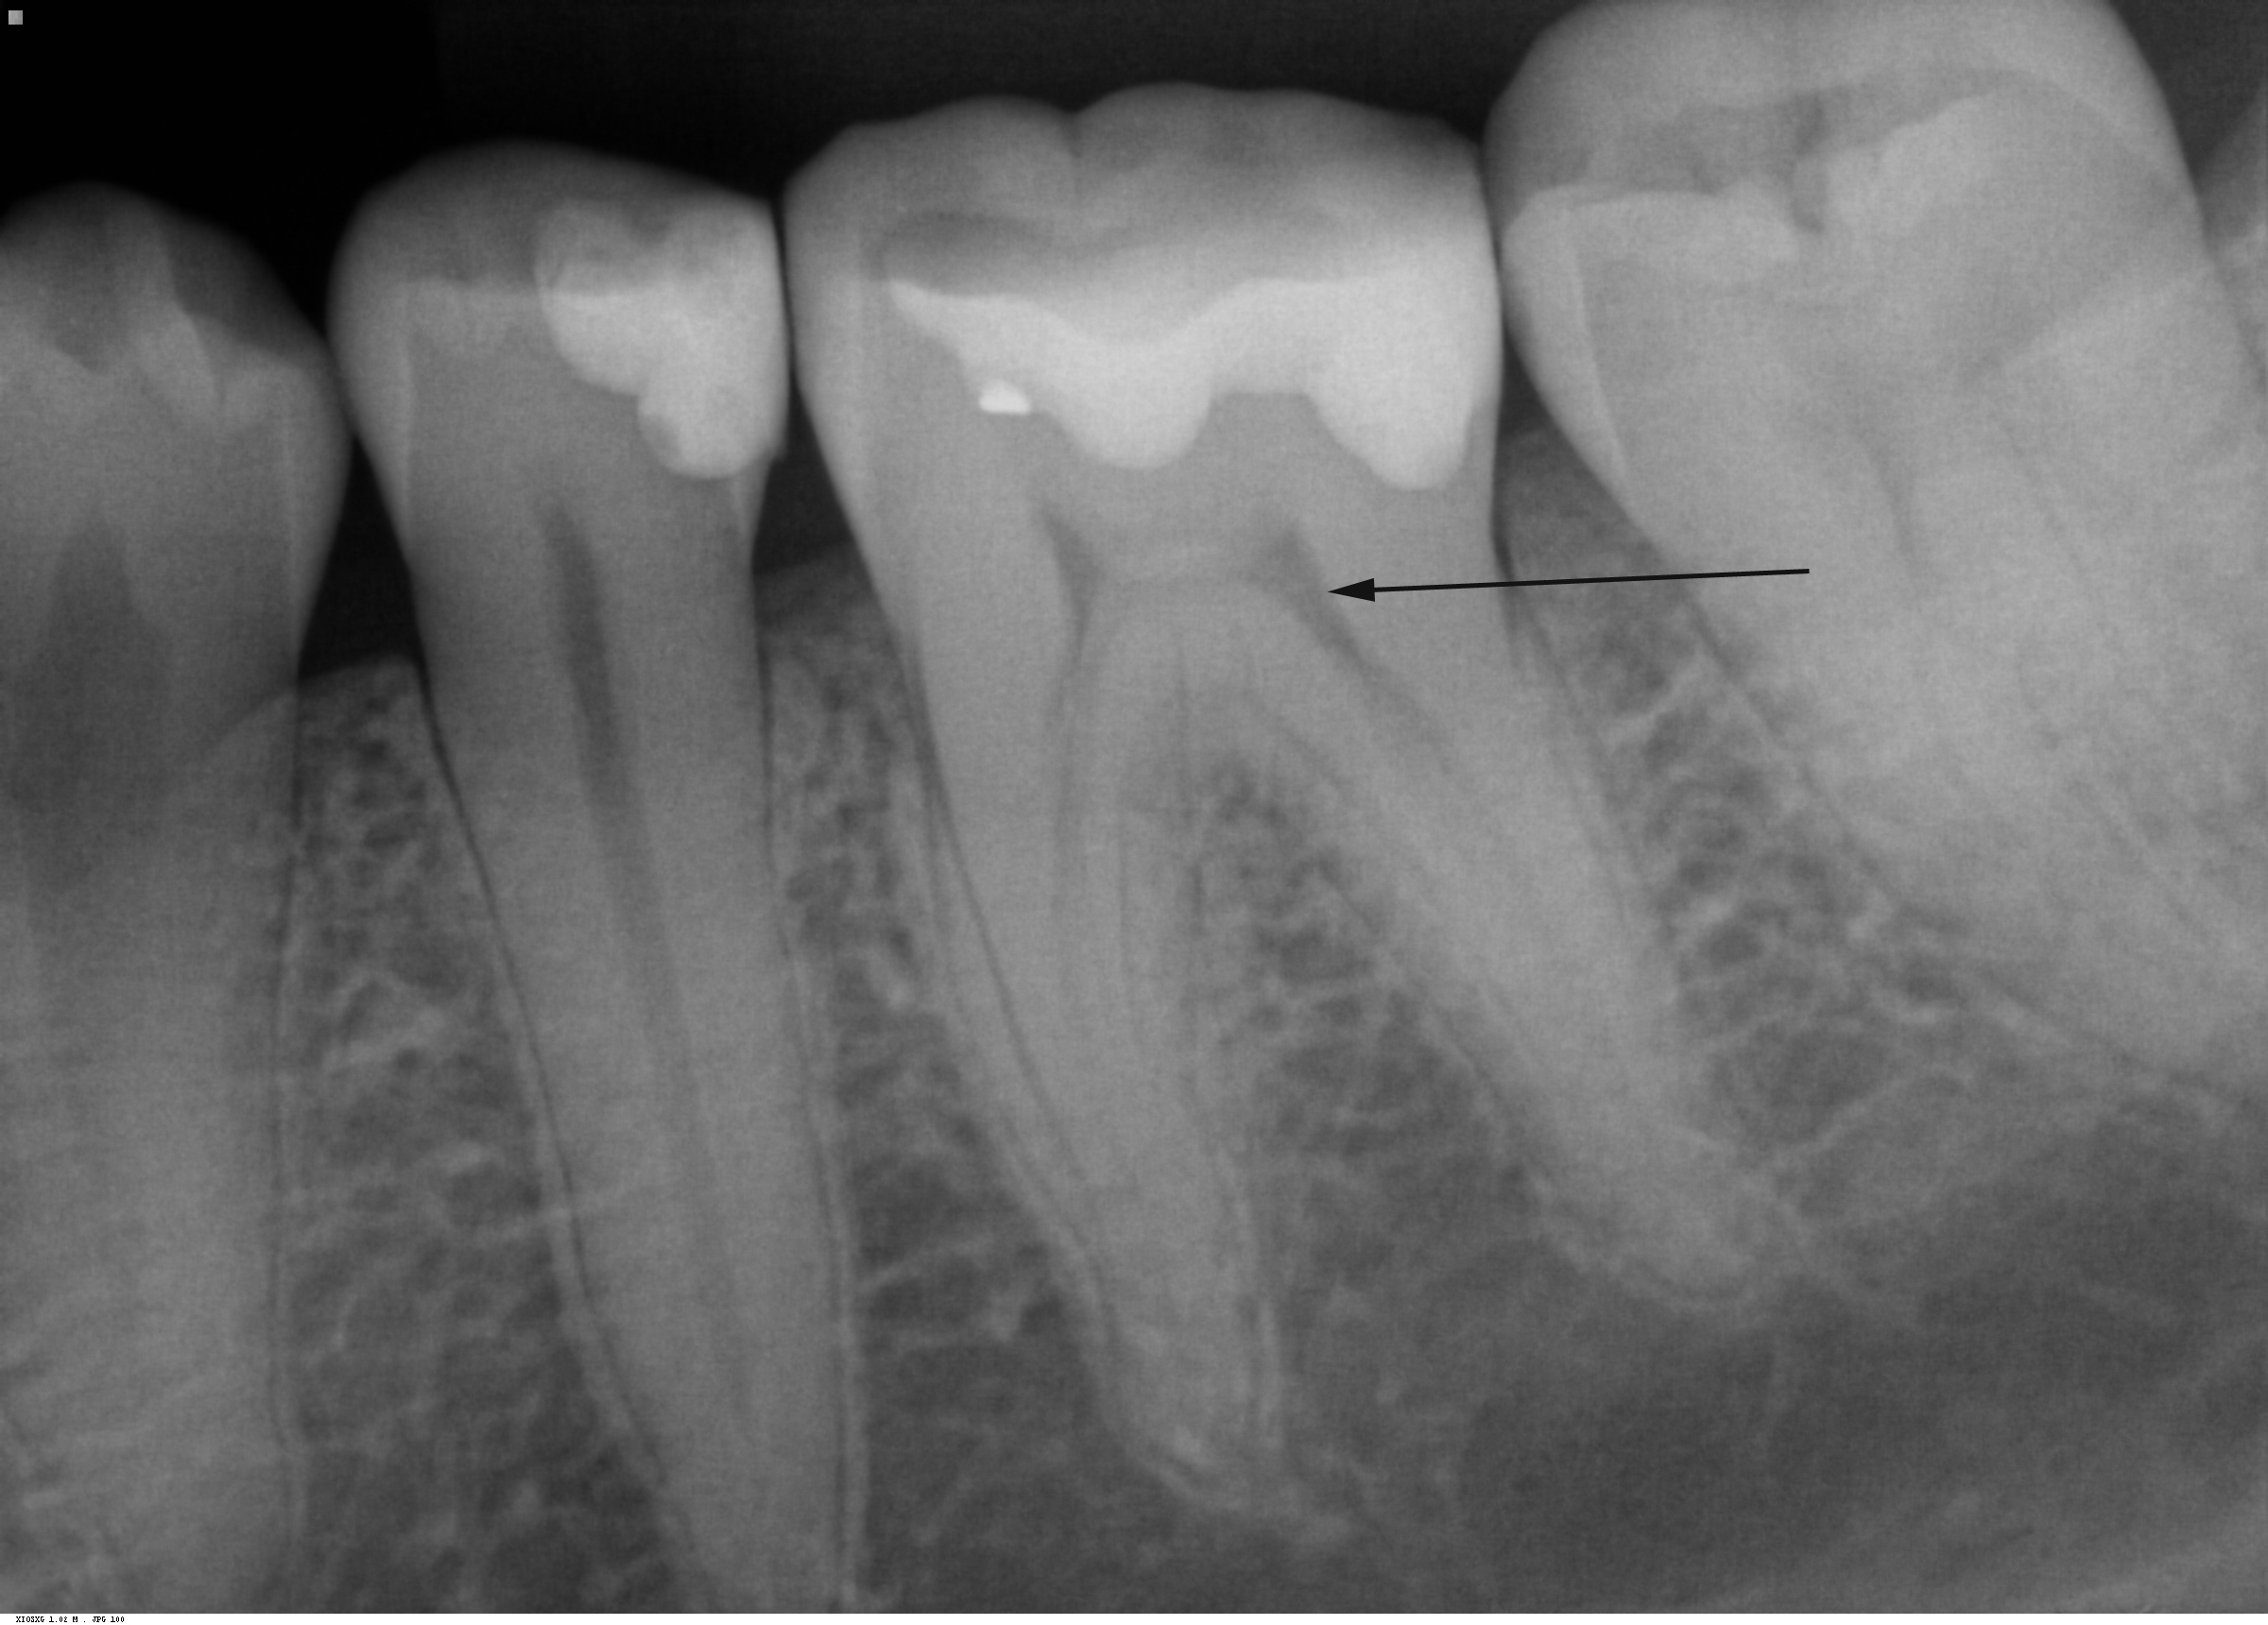

Den sorte pil viser hulrummet i tanden, hvor pulpa sidder.

Billedet viser et røntgenbillede af tænder i underkæben. Pilen peger på en kindtands hulrum (pulpahulen), hvor pulpa er beliggende. Bemærk, at hver rod har et hulrum, der fører ned til rodspidsen, hvor kar og nerver kommer ind i tanden.